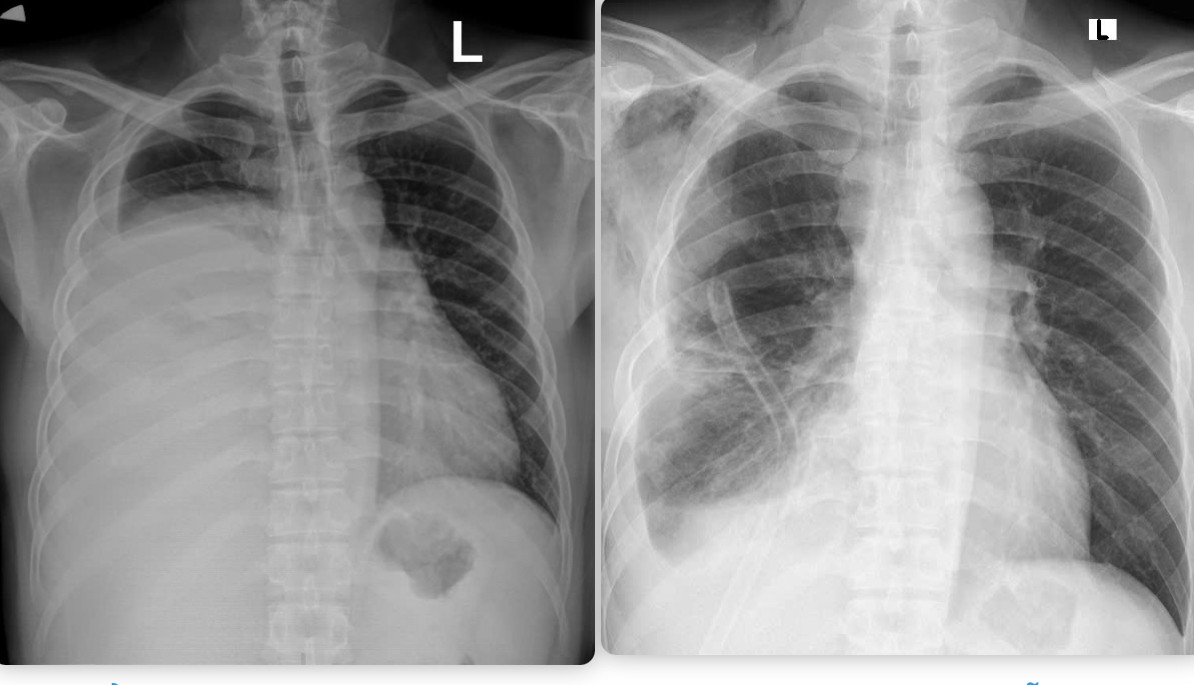

![]() |

| Hình ảnh phim chụp X.quang trước và sau khi phẫu thuật. Hình trước phẫu thuật (bên trái): Khối u xâm chiếm khoang ngực, gây xẹp gần như toàn bộ phổi phải. |